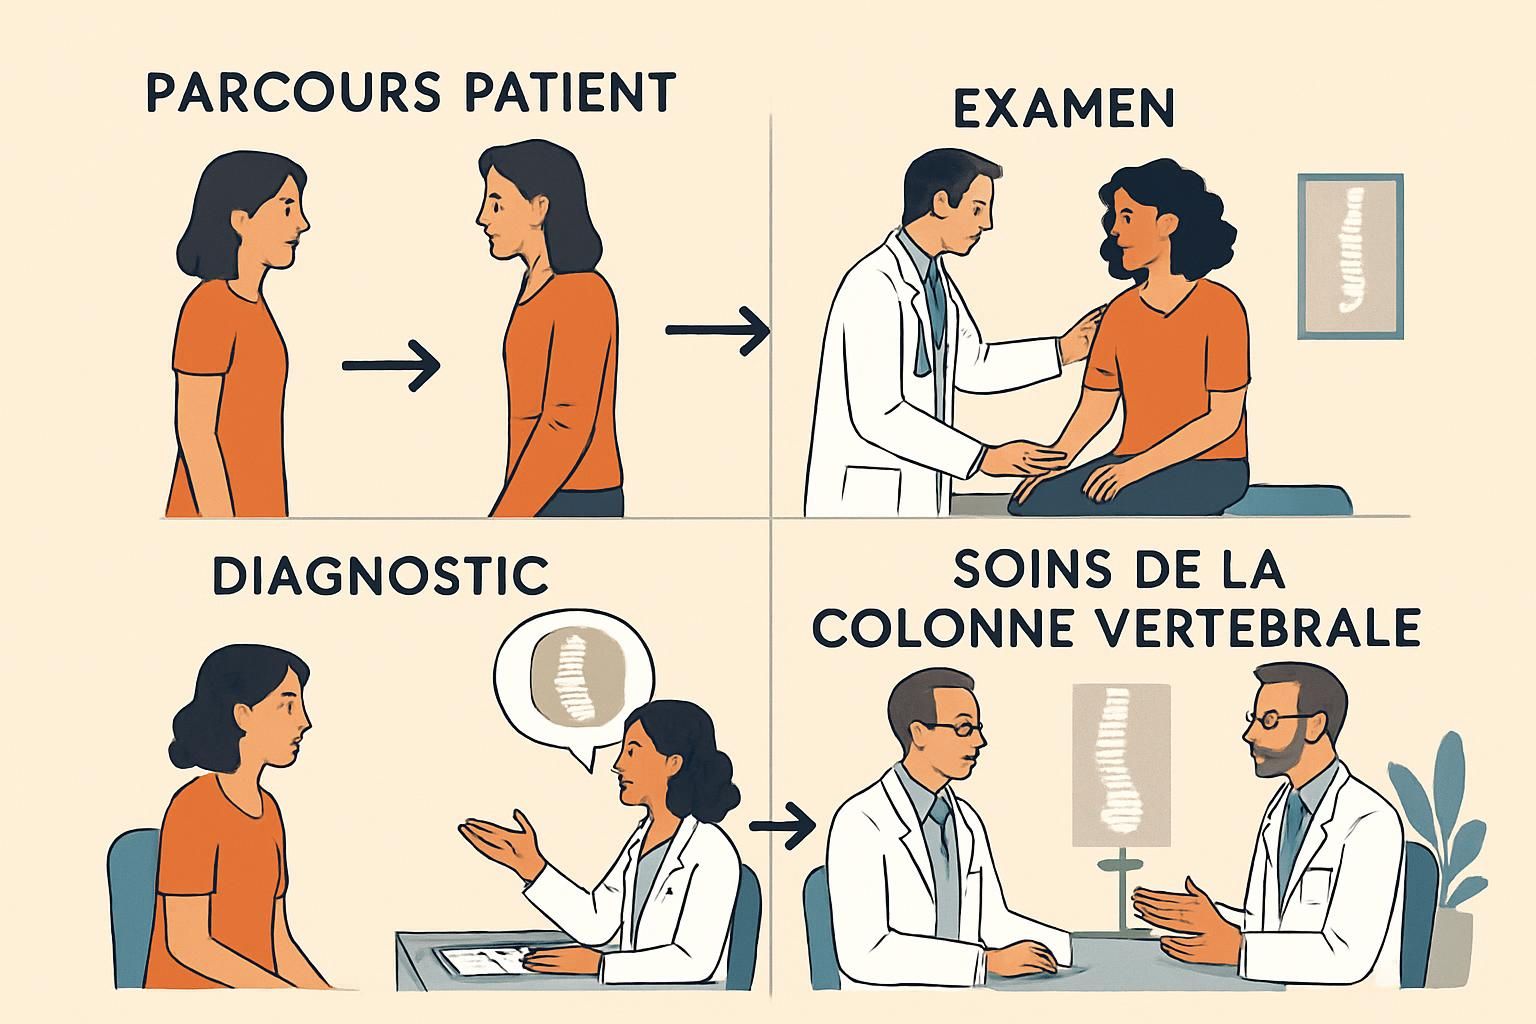

Le parcours patient : une démarche rigoureuse et personnalisée

Avant d’envisager une opération chirurgicale, un parcours patient bien structuré est essentiel. Cela commence par une évaluation approfondie dans une clinique spécialisée où des spécialistes se penchent sur l’historique médical et les examens d’imagerie. L’expertise du Dr. Desforges et de son équipe à la Clinique TAGMED les positionne comme des acteurs clés dans l’accompagnement des patients souhaitant bénéficier de ces innovations.

Une des étapes critiques est le respect d’une période de 3 à 6 mois de traitements conservateurs, comprenant des approches telles que la kinésithérapie et la décompression neurovertébrale. Ces soins permettent souvent d’éviter les interventions chirurgicales, sauvegardant la fonction et la mobilité du cou lorsque cela est possible.